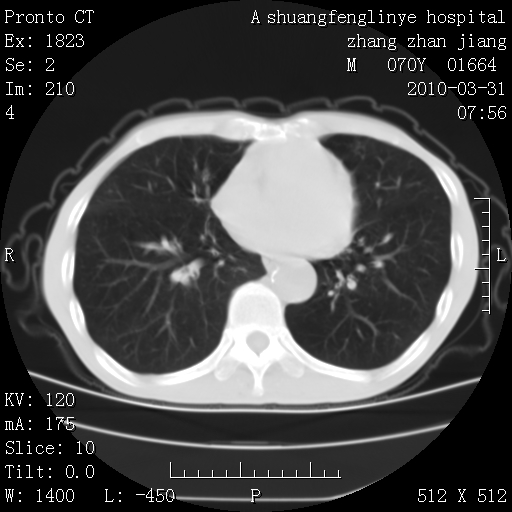

支持,不过左肺中叶那个像陈旧病变的结节要不要单报一下,在图上没看到钙化单报一下放心啊

双上肺继发型tb并左上空洞形成,主动脉冠脉钙化。

1)两肺上叶继发性肺结核并左肺上叶空洞形成。2)冠状动脉及主动脉钙化。